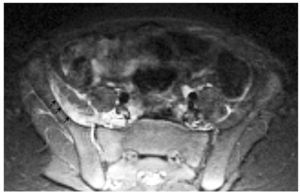

Cuando la ecografía no es concluyente, y persiste una alta sospecha, la técnica de elección es la RM. Spiegel et al12 también demuestran la ventaja de la RM para la identificación de los músculos afectados, los abscesos y la patología subyacente, de forma similar a los hallazgos de nuestra serie (fig. 4). Otros autores como Brigid et al demuestran los hallazgos de la piomiositis en la TC como un aumento de tamaño del músculo afectado, pérdida de la nitidez de los planos musculares y presencia de colecciones hipodensas en caso de abscesos intramusculares; en su serie concluyen que tanto la TC como la RM son útiles para la identificación de los músculos afectados y de abscesos20.

Fig. 4. (A) Afectación osteoarticular. Aumento de señal en el hueso ilíaco izquierdo en secuencia coronal STIR. (B) Afectación osteoarticular. Secuencia axial FSE T2: afectación de la articulación interapofisaria con mínimo derrame articular. (C) Afectación osteoarticular. Secuencia coronal STIR: derrame en la articulación sacroilíaca derecha.